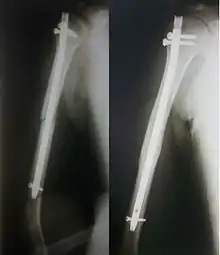

Внутрикостный остеосинтез

Внутрикостный (интрамедулярный) остеосинтез может быть закрытым и открытым. При закрытом после сопоставления отломков по проводнику через небольшой разрез вдали от места перелома вводят под рентген-контролем фиксатор. При открытом зону перелома обнажают, отломки репонируют и в костный канал сломанной кости вводят фиксатор.